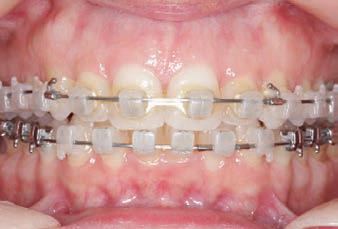

CLASS II DIV.1 - Marra

PROVIDED BY: DR. LUIS CARRIÈRE

INITIAL - 4/4/18

PROGRESS 1 - 26/9/18 - Class I platform accomplished in 5.75 months with Motion 3D COLOR Appliance

PROGRESS 2 - 26/9/18 - Placement of the SLX 3D Clear Brackets

[CONTINUED ON NEXT PAGE]

with M-ONE .015 Cu Nitanium 27°

PROVIDED BY: DR. LUIS

PROGRESS 3 - 30/10/18 - With M-TWO .020 x .020 Cu Nitanium 35° archwire

PROGRESS 4 - 27/11/18 - 3 links power chain: 5, 4, bypass 3 to crimp hooks

PROGRESS 5 - 13/3/19 - With M-TWO .020 x .020 Cu Nitanium 35° archwire

PROGRESS 6 - 1/8/19 - With M-THREE.019 x .025 Beta Titanium wire

52 HENRY SCHEIN ORTHODONTICS

FINAL - 10/10/19 - Appliances removed AFTER

PROGRESS 7 - 10/10/19 - Final day in SLX 3D Clear Brackets BEFORE